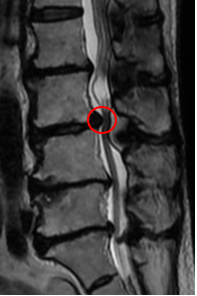

治療前

腰椎MRIを確認したところ、赤い枠で示されているL3/4が強く狭窄しているのを認めました。そのため、他院の診断通り「腰部脊柱管狭窄症」と診断しました。

右足の痛みや痺れの原因も、この狭窄が原因だと考えられます。